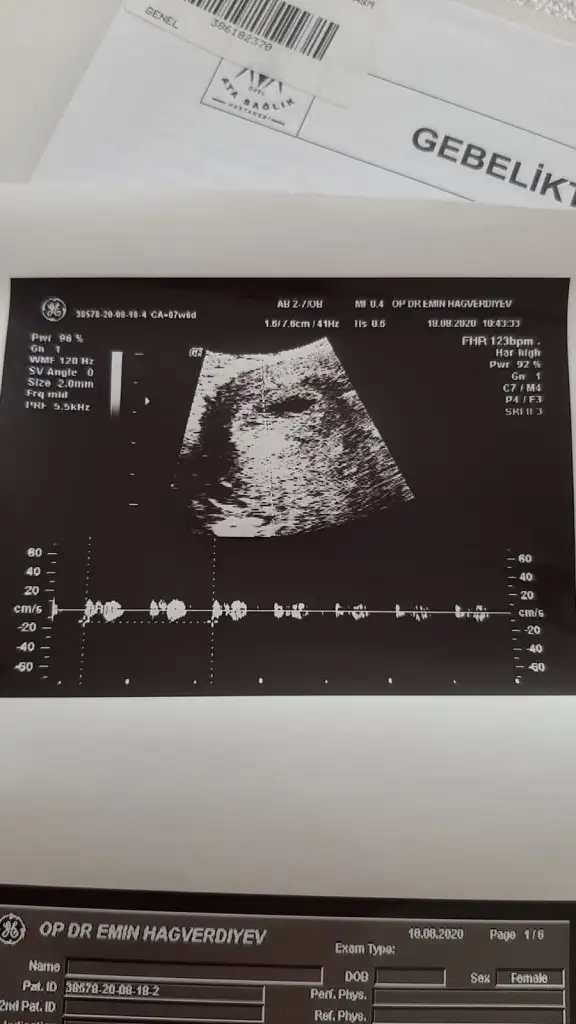

Kız buna göre ama en iyi 11 12 13 haftalar olmalıBenimde bakabilir misiniz 7 haftalık vajinadan ultrasondan çekildi

Teşekkür ederim ilk oğlumda da erkek demiştiniz çıkmıştı inşallah buda öyledir hayırlısıyla inşallahKız buna göre ama en iyi 11 12 13 haftalar olmalı

Kız gibi ama en iyi 11 12 13 haftalar olmalı